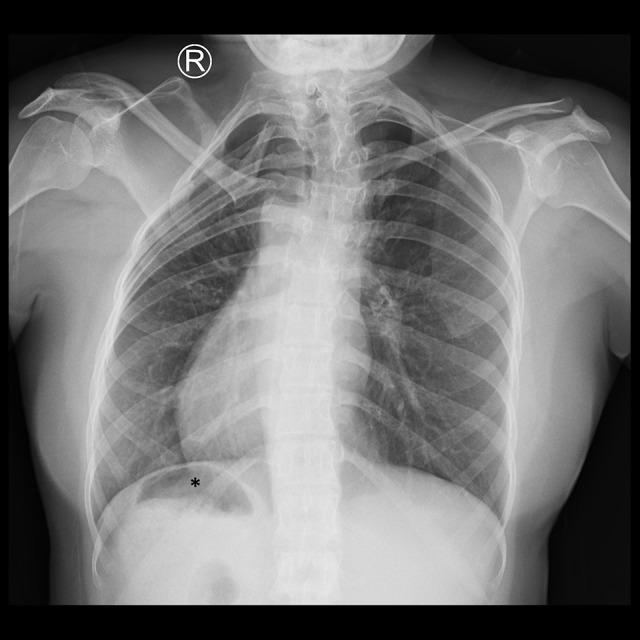

BACKGROUND Mayer-Rokitansky-Kuster-Hauser (MRKH) syndrome is a complex disorder of the female reproductive system that results in an absent uterus and vagina. MRKH syndrome can be an isolated anomaly (typical) or accompanied by other organ anomalies (atypical). Due to the similarity of symptoms with other congenital gynecological diseases, imaging modalities remain the most important tools in establishing the diagnosis by visualizing internal genital and detecting possible organ malformations. CASE REPORT We present a very rare case of a female with primary amenorrhea. Pelvic magnetic resonance imaging (MRI) showed the absence of a uterus and vagina with possible Mullerian remnants, as well as an incidental finding of a right ectopic kidney. Abdominal ultrasonography and chest X-ray showed that the patient also had situs inversus totalis. CONCLUSIONS MRKH syndrome may be associated with situs inversus totalis due to possible early embryologic malformations causing both conditions; however, the exact mechanism is still unknown. This report should serve as a more recent attempt to question whether situs inversus totalis is related to MRKH and to emphasize the importance of imaging modalities, especially MRI, in establishing the diagnosis of MRKH syndrome and the associated malformations.

我们介绍了一例女性原发性闭经的极罕见病例。盆腔磁共振成像(MRI)显示子宫和阴道缺失,可能有苗勒管残余物,以及右侧异位肾的意外发现。腹部超声和胸部 X 线检查显示患者还患有全内脏转位。